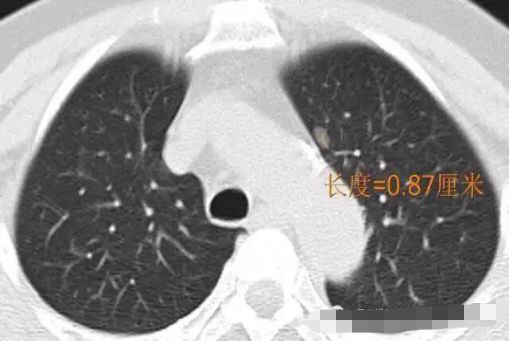

病例2

随访3年,GGO直径基本没有变化

2013年12月

2014年7月

2015年5月

2016年10月